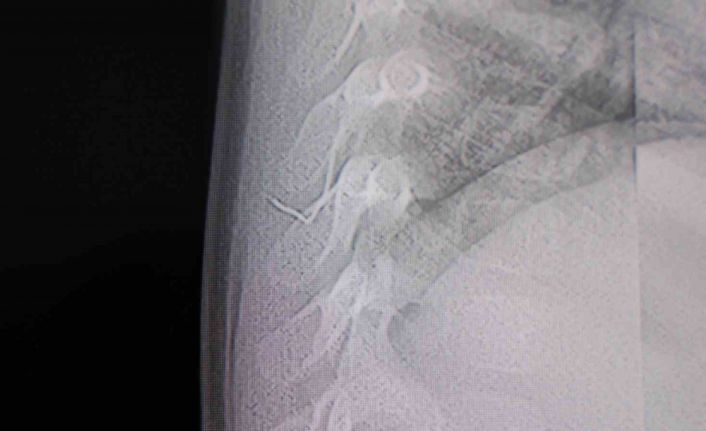

Kahramanmaraş’ta sırt üstü yatmak istemeyen, yatırıldığında ağlama ve huzursuzluğu nedeniyle hastaneye götürülen bir yaşındaki bebeğin sırtından akciğer zarına doğru ilerleyen 2 santimetrelik zımba teli çıktı.

Alınan bilgiye göre, Kahramanmaraş’ta farklı ortopedi, çocuk cerrahisi ve beyin cerrahisi kliniklerine başvurusu yapılan bir yaşındaki bebeğin, sırt bölgesinde yabancı bir cisim olduğu ancak müdahalenin zor olduğu ve 8 yaşına kadar beklenmesi gerektiği bildirildi. Aile, bebekleri için son olarak HG Hospital’e başvurdu. HG Hospital Beyin ve Sinir Cerrahisi Uzmanı Prof. Dr. İdris Altun tarafından yapılan tetkiklerde, yabancı cismin cilt altında, omurilik kanalına yakın bir bölgede olduğu ve akciğer zarına doğru ilerlediği belirlendi. Hasta, genel anesteziye alınmadan, lokal anestezi ve sedasyon eşliğinde ameliyata alındı. Yapılan müdahalede yabancı cisim tamamen çıkarıldı. Çıkarılan cismin, ince zımba teline benzer metal bir tel olduğu ve yaklaşık 2 santimetre uzunluğunda bulunduğu tespit edildi. Hasta, aynı gün taburcu edildi.

Konuya ilişkin açıklama yapan Prof. Dr. İdris Altun, "Sırtında yabancı bir cisim olduğu söylenmiş ancak çıkarılamayacağı ve 8 yaşına kadar beklenmesi gerektiği ifade edilmişti. Bize başvurduğunda yaptığımız tetkiklerde, cilt altında, omurilik kanalına çok yakın ve akciğer zarına doğru ilerleyen bir yabancı cisim tespit ettik. Hastamızı tamamen uyutmadan, lokal anestezi ve sedasyon eşliğinde müdahale ederek lezyonu tamamen çıkardık. Çıkardığımız cismin ince zımba teline benzer, yaklaşık 2 santimetre uzunluğunda metal bir tel olduğunu gördük. Bu yabancı cisim alınmasaydı, bölgede enfeksiyon gelişebilirdi. Enfeksiyon sonucu omurilik kanalında ciddi hasarlar oluşabilir, çocuk büyüdükçe cismin hareket etmesine bağlı olarak omurilikte zedelenmeler meydana gelebilirdi. Ayrıca yana doğru ilerleyerek akciğer zarına ve akciğere batma riski vardı. Bu da enfeksiyona ve ilerleyen süreçte tümörle karışabilecek tablolara neden olabilirdi. Şu an hastamız gayet sağlıklı. Gerekli kontrolleri yaptık ve aynı gün taburcu ettik" dedi.